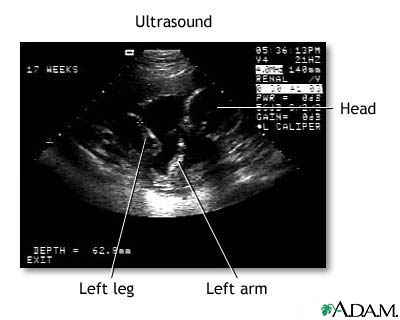

This is a normal fetal ultrasound performed at 17 weeks gestation. The development of the brain and nervous system begins early in fetal development. During an ultrasound, the technician usually looks for the presence of brain ventricles. Ventricles are spaces in the brain that are filled with fluid. In this early ultrasound, the ventricles can be seen as light lines extending through the skull, seen in the upper right side of the image.